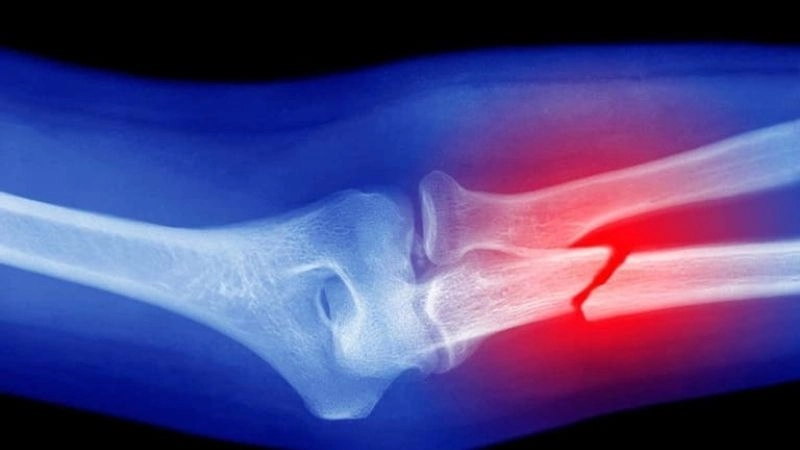

Tình trạng xương bị gãy sẽ có các biểu hiện khác nhau

Tình trạng xương bị gãy sẽ có các biểu hiện khác nhau, tùy thuộc vào vị trí gãy, mức độ nghiêm trọng của chấn thương, tuổi tác và sức khỏe chung của người bệnh.

Khu vực gãy xương thường có một số triệu chứng đặc trưng như:

- Đau, đặc biệt là khi di chuyển hoặc chạm vào vùng bị thương

- Sưng tấy, đỏ, bầm tím ở vùng xương bị tổn thương

- Tay chân cong, xoắn, biến dạng bất thường ở vị trí gãy

- Cảm giác nóng ran ở xương hoặc khớp bị ảnh hưởng

- Chảy máu, xương nhô ra nếu đó là một vết gãy hở

- Có thể nghe thấy tiếng răng rắc khi chấn thương xảy ra

- Mất chức năng vùng bị chấn thương

Trong những trường hợp nghiêm trọng hơn, người bệnh sẽ cảm thấy chóng mặt, buồn nôn, ngất xỉu…